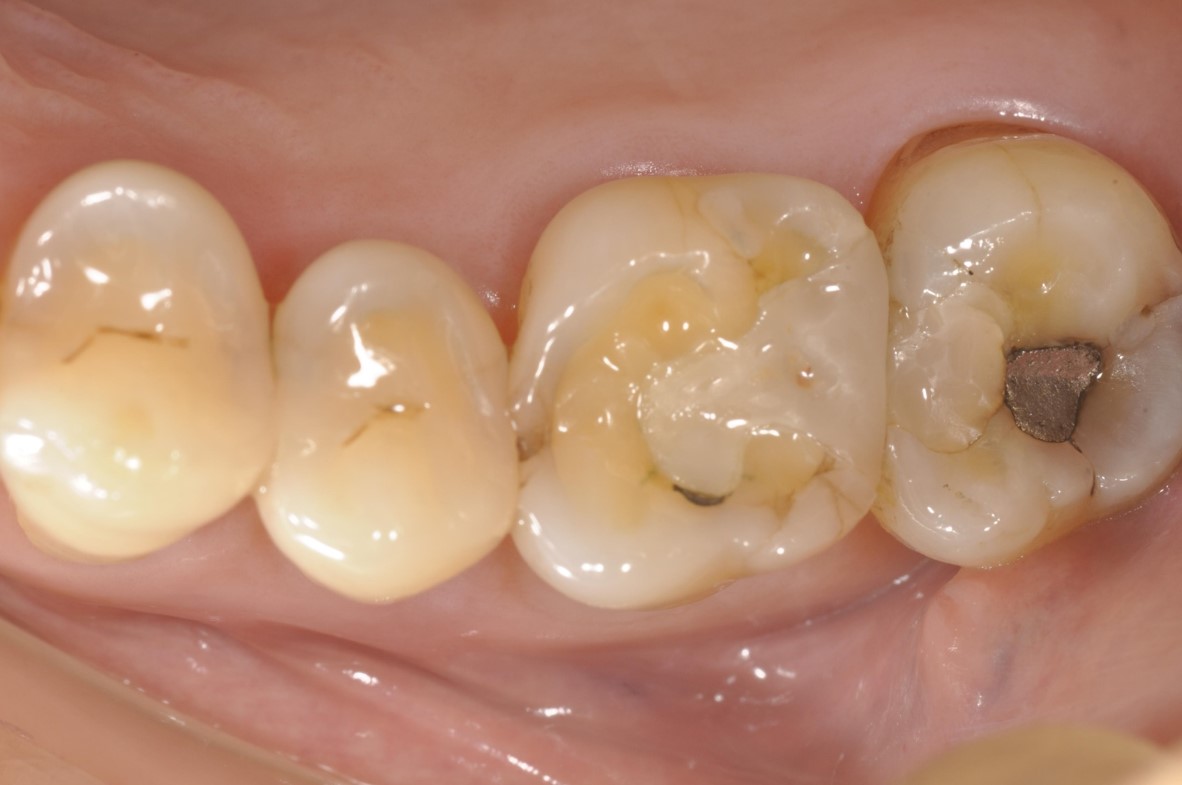

治療前,因磨耗,導致原瓷塊斷裂

治療前,牙髓仍完整